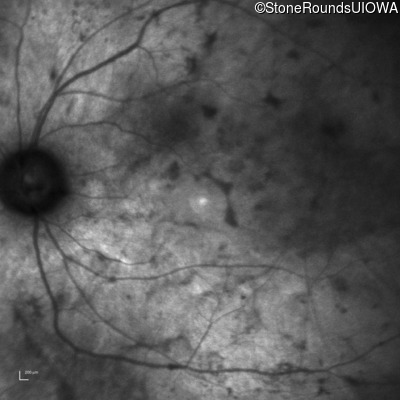

Infrared Fundus Photograph - Right - No Light Perception

Exemplar

Infrared Fundus Photograph - Left - Light Perception